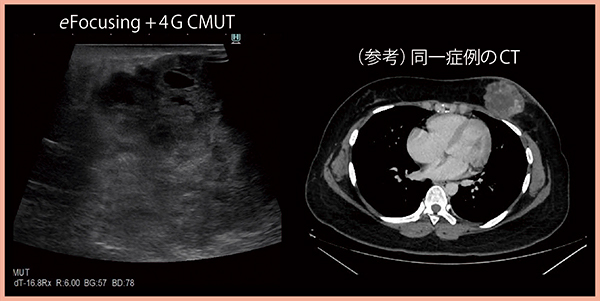

図3は,乳房下部に6cm大の腫瘤があり,周囲には浮腫性変化が認められるほか,アトピー性皮膚炎で表皮が荒れているなど,条件の厳しい症例であるが,eFocusingと4G CMUTを用いることで病変の内部まで描出が可能であった。

図3 eFocusingと4G CMUTによる病変の良好な描出(6cm大の乳房腫瘤)